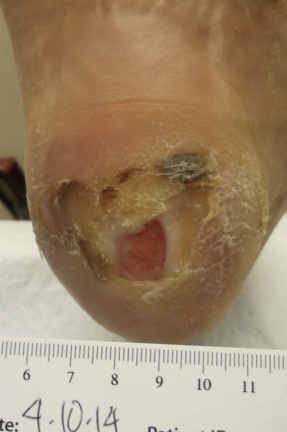

3 Days post ‘spur removal’ surgery. Patient returned with severe pain, swelling and ascending cellulitis. Surgical site infected with Streptococcus sp Staphylococcus aureus

Post Surgical Infection - Clinical Case

Culture Negative at 10 Days

Day 29

Approximately 1 week Post Closure

Day 14

using SilvaKlenz and Silvion

BID cleansing with SilvaKlenz, flushed with Silvion. Wound packed with Silvion moistened 1/4 inch strip